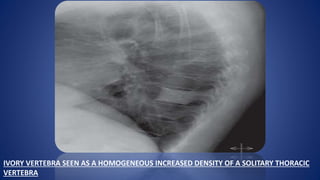

IVORY VERTEBRA SEEN AS A HOMOGENEOUS INCREASED DENSITY OF A SOLITARY THORACIC

VERTEBRA

HODGKIN’S LYMPHOMA OFBONE • Occurs more commonly as a secondary manifestation of systemic hodgkin’s disease . Rarely as a orimary bone involvement • Main site – Vertebral body of the lower thoracic and upper lumbar spine . • Radiologically , most lesions are osteolytic . • Occasionally , a marked sclerotic reaction can be seen as an ivory vertebra . • In the lumbar vertebrae , lytic destruction is more common with exuberant periosteal reaction .

IVORY VERTEBRA SEENAS A HOMOGENEOUS INCREASED DENSITY OF A SOLITARY THORACIC VERTEBRA